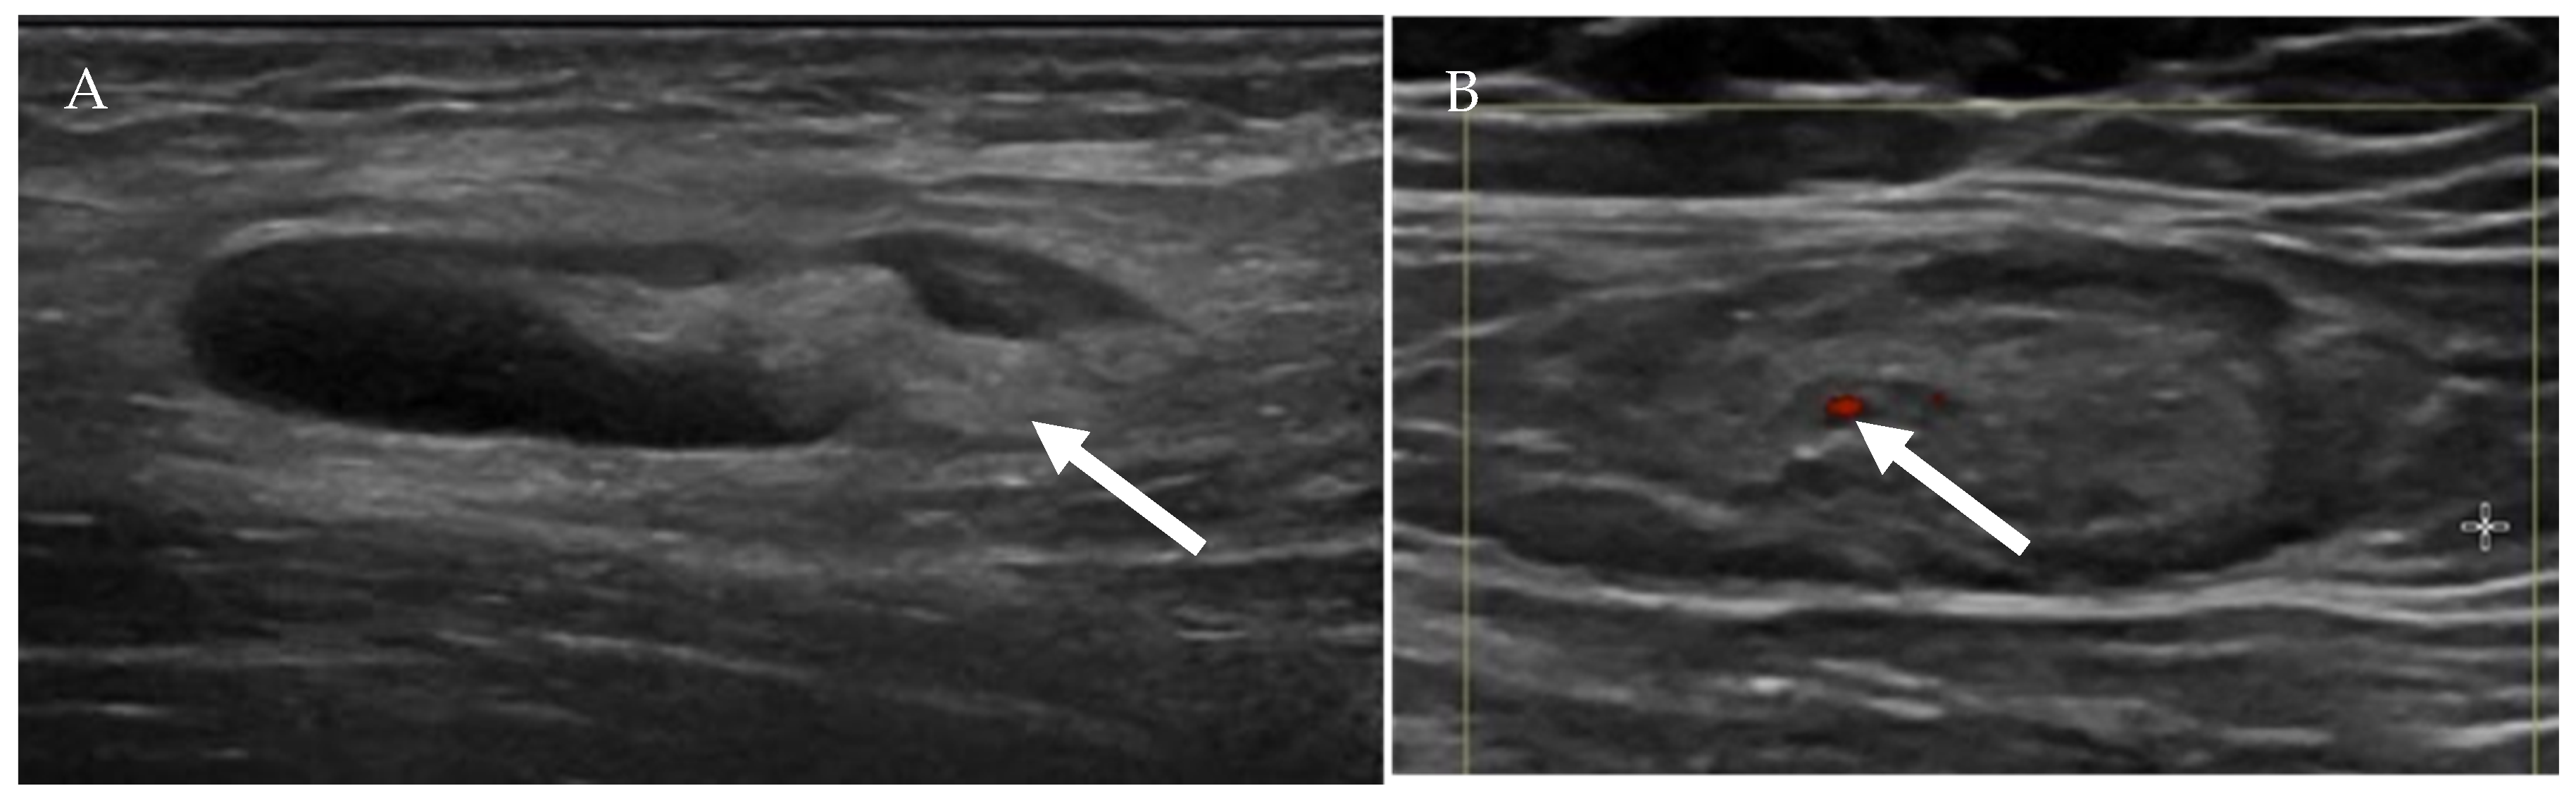

4.1.1. Ultrasound Evaluation of the Lymphatic System

- Prativadi, R.; Dahiya, N.; Kamaya, A.; Bhatt, S. Chapter 5 Ultrasound Characteristics of Benign vs Malignant Cervical Lymph Nodes. Semin. Ultrasound CT MRI 2017, 38, 506–515. [Google Scholar] [CrossRef]

- Wang, B.; Zhang, M.K.; Zhou, M.P.; Liu, Y.; Li, N.; Liu, G.; Wang, Z.L. Logistic Regression Analysis of Conventional Ultrasound, and Contrast-Enhanced Ultrasound Characteristics. J. Ultrasound Med. 2021. [Google Scholar] [CrossRef]

- Dudea, S.M.; Lenghel, M.; Botar-Jid, C.; Vasilescu, D.; Duma, M. Ultrasonography of superficial lymph nodes: Benign vs. malignant. Med. Ultrason. 2012, 14, 294–306. [Google Scholar]

- Vassallo, P.; Wernecke, K.; Roos, N.; E Peters, P. Differentiation of benign from malignant superficial lymphadenopathy: The role of high-resolution US. Radiology 1992, 183, 215–220. [Google Scholar] [CrossRef]

- Ahuja, A.; Ying, M. Sonographic evaluation of cervical lymphadenopathy: Is power Doppler sonography routinely indicated? Ultrasound Med. Biol. 2003, 29, 353–359. [Google Scholar] [CrossRef]

- Ahuja, A.T. Ultrasound of malignant cervical lymph nodes. Cancer Imaging 2008, 8, 48–56. [Google Scholar] [CrossRef]

| US Criteria | Benign Lymph Node | Malignant Lymph Node |

|---|---|---|

| Size | <1 cm in short axis | ≥1 cm in short axis |

| Shape | Oval or elliptical | Round |

| Border | Indistinct | Sharp |

| Echogenicity | Hypoechoic | Very hypoechoic |

| Hilum | Maintained fatty hilum | Absent fatty hilum |

| Vascularity | Avascular or hilar vascularity | Peripheral or mixed |

| Resistive index | Low | High |